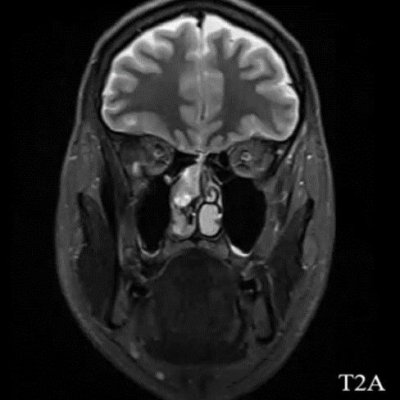

- A) Koronal T2A görntüde sağ süperior nazal kavite içerisinde hafif ekpansil karakterde, keskin sınırlı, nisbeten lobüle konturlu heterojen ara sinyal intensitye sahip yumşak doku lezyonu izleniyor (oklar).

- Estezionöroblastom görüntülemede tipik olarak nazal kavite tavanında, lamina cribrosa düzeyinden köken alan, etmoid sinüsler, orbita ve anterior kraniyal fossaya yayılım gösterebilen lobüle, agresif karakterli bir yumuşak doku kitlesi olarak izlenir ve sıklıkla komşu kemik yapılarda destrüksiyona neden olur. MR’da lezyon genellikle T1-ağırlıklı serilerde izo/hipointens, T2-ağırlıklı serilerde hiperintens sinyal özelliği gösterir ve kontrast sonrası heterojen güçlü kontrastlanma izlenir. İntrakraniyal uzanım varlığında tümör ile frontal lob parankimi arasında izlenen peritümöral periferik kistik değişiklikler, estezionöroblastom için literatürde tanımlanmış ayırt edici ve spesifik bir MR bulgusudur.